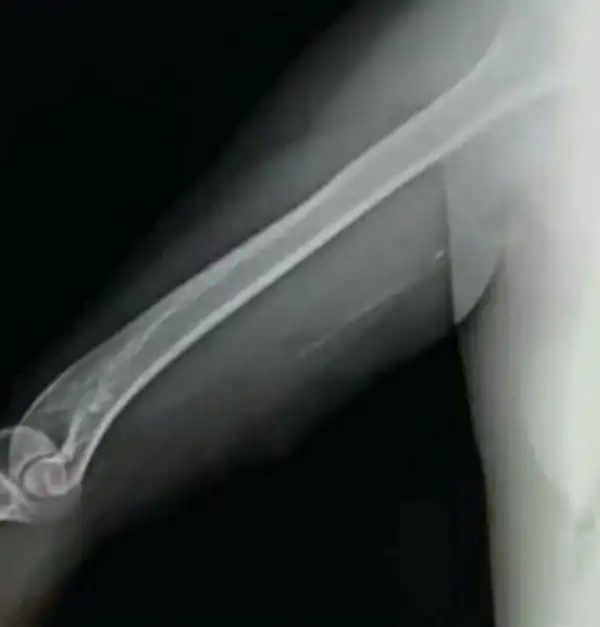

38-летний Хосе Даниэль Лопес работал в городах Ла-Виктория и Маракай. Он подделал медицинскую степень и сам научился делать операции. Жертвами Лопеса стали как минимум 25 женщин, которым он имплантировал пластиковые палочки в руку, утверждая, что это устройство «Импланон», которое помогает бороться с нежелательной беременностью. В итоге многие из его пациенток, как вы уже догадались, залетели..